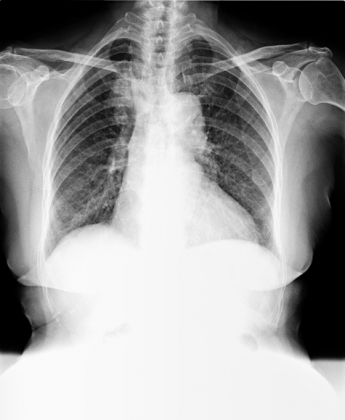

異常胸部X光影像

醫學影像..X光影像